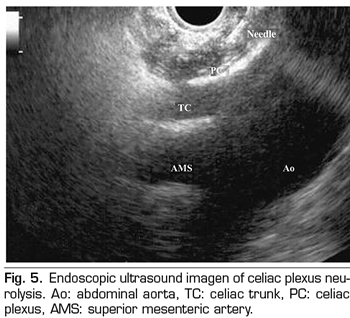

Endoscopic ultrasound offers the advantage of larger visualization of the celiac plexus at a short proximity, allowing larger precision and safety in the administration of the neurolytic agent and avoiding injection into vascular structures through the use of Doppler (37) (Figure 5). However, the studies supporting endoscopic ultrasound neurolysis, considered similarly to percutaneous technique as a rescue therapy, are limited to retrospective uncontrolled studies (38). Pauli et al. published a meta-analysis that concludes that this technique achieves an 80% pain reduction in patients with pancreatic cancer (39). Some studies show a slight decrease in opioid consumption, but without strong scientific evidence.